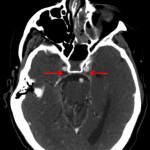

- Lack of opacification of the bilateral cavernous sinuses

- Lobulated anterior communicating artery aneurysm involving both A1 and A2 segments

- Dural venous and cavernous sinus thrombosis

- ACA aneurysm

Dural venous sinus thrombosis with multiple areas of segmental thrombus in the nondominant left transverse sinus and occlusive thrombus extending from the transverse-sigmoid sinus junction into the left internal jugular vein. Lack of opacification of the bilateral cavernous sinuses is concerning for bilateral cavernous sinus thrombosis. There is also thrombosis of the left superior ophthalmic vein and nonocclusive thrombus in the right jugular bulb. No acute hemorrhage or mass effect.

Lobulated anterior communicating artery aneurysm involving both A1 and A2 segments measuring 5 x 8 mm.